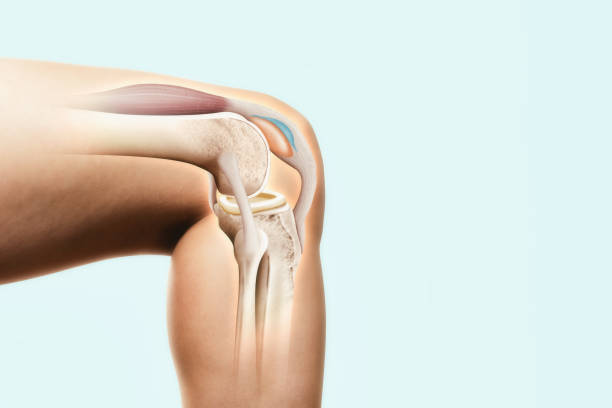

슬개골염은 슬개골 연골과 연결된 퇴행성 질환으로, 무릎 관절 내부에서 연골의 변성이 진행됨에 따라 발생합니다. 무릎 통증, 관절 강직, 충수성 부종 등의 증상을 일으키며, 보행이나 운동 시 통증이 더욱 심해질 수 있습니다. 치료는 운동 치료, 약물 치료, 수술적 치료 등이 있으며, 초기 단계에서 조기에 진단하고 치료를 시작하는 것이 중요합니다.

무릎 관절염은 무릎 관절의 연골과 주변 조직들이 염증을 일으키는 질환으로, 노화, 과부하, 외상 등이 원인이 됩니다. 무릎 관절이 불안정해지고 염증이 발생하면 통증, 부종, 관절 강직 등의 증상이 나타납니다. 운동, 체중 감량, 약물 치료 등이 치료 방법으로 사용됩니다. 특히 중증도가 높은 경우 수술 치료가 필요할 수 있습니다.